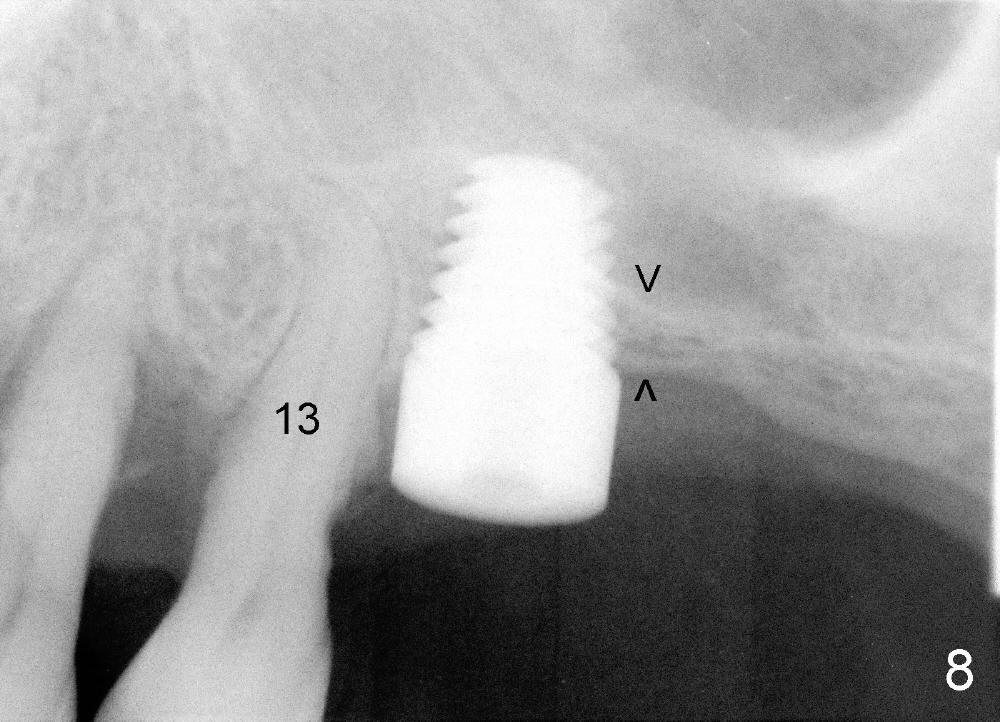

Mr. Wu (54 years old) is also scared of dentistry. He postpones implants for several years. One day he decides to get implant treatment. Easy placement is tried at the sites of #21 and then #7 (Fig.2). He is doing fine postop on both these occasions. Attention is turned to the site of #14 with 2.85 mm bone in height distally (Fig.5 CT sagittal section). The white area represents the crown at the site of #14 (CT scan stent). The coronal section also shows limited bone height (~3 mm) (Fig.6). A 6x11 mm tapered implant is planned to get as large as implant/bone surface area, particularly the mesial aspect (Fig.5,6). Tatum bone expansion technique is used to created osteotomy (#15 blade, BS 4-6 mm, BB 4-10 mm at the depth ~8 mm, RT 2-5 mm at 11 mm, no drill). A 6x11 mm tapered tap is applied (Fig.7 T). It appears that the tap tilts mesially. Adjustment of trajectory is made with RP, RB 4-5 mm at 11 mm and 7x11 mm tapered tap (with resistance). The corresponding implant is placed with >60 Ncm (Fig.8; distal bone quite narrow (between arrowheads). The patient is doing great a month postop with no sign of infection or mobility.